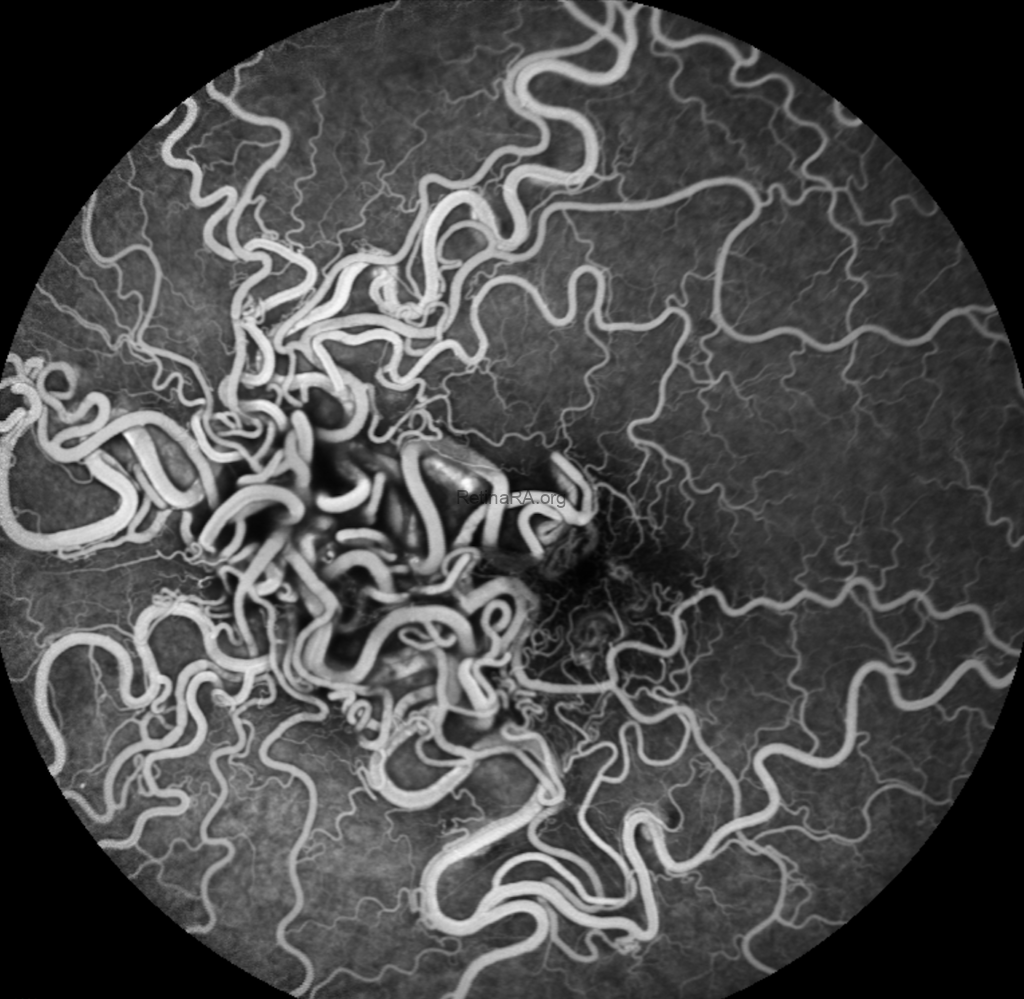

OS: Congested, tortuous vessels with a vasoproliferative-appearing lesion, highly suggestive of racemose hemangioma

FA Findings:

OS: Rapid filling without leakage, neovascularization, or ischemia

Diagnosis is racemose hemangioma. The patient was referred for CT angiography to assess cerebrovascular involvement.

Racemous hemangioma of the retina (RRH) is a rare congenital retinal arteriovenous malformation characterized by anomalous arteriovenous communications. Thirty percent of patients with RRH have also been found to have Wybrun-Mason syndrome, an arteriovenous malformation in the brain. Therefore, it is important to exclude this pathology with brain MRI.